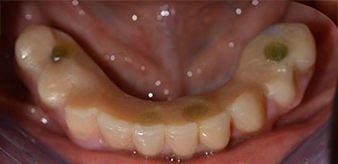

The 64-year-old patient presented with residual dentition of teeth 38, 33 and 43 and a clasp denture in the mandible (Fig. 1 and 2).

Following an explanation of the various treatment options open to her, the patient decided on extraction of the residual dentition in the mandible, an immediate implantation and treatment with the Fast & Fixed method (bredent medical), whereby the provisional fixed denture is screwed onto four implants on the same day as the surgery. The goal was to operate on the patient on the Friday so that she could assist in the oral examinations on the following Monday.